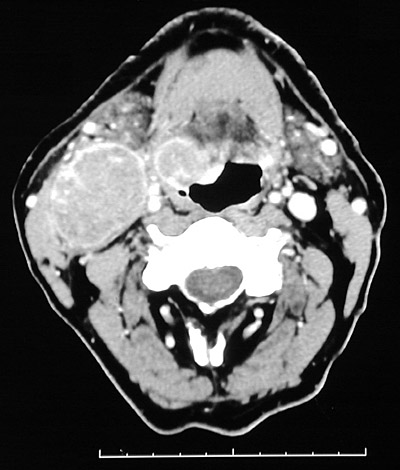

There is a prominent squamous cell carcinoma involving the right posterior base of the tongue in the region of the lingual tonsil. There is a large mass of adjacent lymph nodes with metastatic carcinoma.